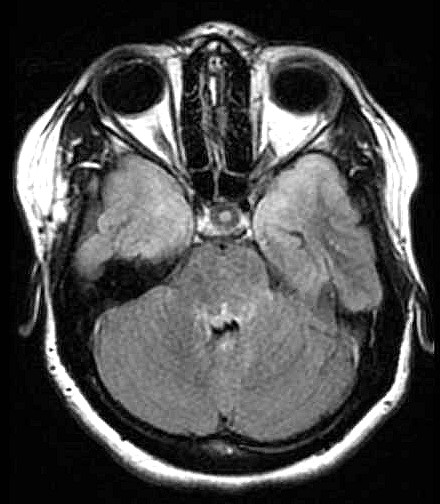

| Fem. 17a. |

| Nódulo sólido homogêneo preenchendo o III ventrículo, com limites precisos, com hipossinal em T1 e hipersinal em T2 e FLAIR, que se impregna por contraste paramagnético. Lesão menor implantada no assoalho do IV ventrículo provavelmente representa disseminação por via liquórica. |

| F. 17a. Tumor teratóide rabdóide atípico de III ventrículo. RM | HE | VIM, GFAP | HHF35, desmina, 1A4 | AE1AE3, EMA |